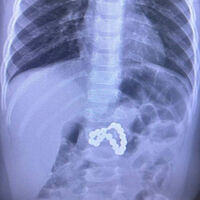

Врачи Центра охраны материнства и детства Сургута спасли девочку, которая поступила в больницу в тяжелом состоянии, проглотив магниты от браслета. Об этом в Telegram-канале сообщила руководитель центра Лариса Белоцерковцева.

Ребенок проглотил несколько магнитных шариков от детского браслета, в больницу ее доставили в тяжелом состоянии. Было принято решение о проведении экстренного хирургического вмешательства, инородные тела вызвали перфорацию кишечника и желудка.